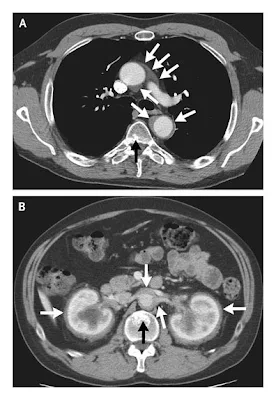

La TAC de tórax llevada a cabo en este hospital, mostró una densidad de partes blandas que se extendía desde el origen de la arteria subclavia izquierda hasta el abdomen, rodeando circunferencialmente a la aorta, de un grosor que iba de los 5 a los 10 mm (Figura 2A). En el abdomen (Figura 2B), este tejido rodeaba la aorta y las arterias renales y terminaba justo antes de la bifurcación de la aorta. El tejido rodeaba los riñones, que tenían hidronefrosis leve. Había focos escleróticos en el húmero, cuerpos vertebrales (Figura 2B), y los huesos ilíacos. Yo revisé las tomografías llevadas a cabo en otro hospital y encontré evidencias de tejidos anormales alrededor de la aorta y los riñones 4 y 2 años antes, aunque los hallazgos no eran tan notables como se observa en las imágenes actuales.

Figura 2 TAC de Tórax y Abdomen.

Una TAC con contraste de tórax a nivel de la carina (Panel A) muestra una anomalía de partes blandas que rodea la aorta ascendente, con un grosor de 5 a 10 mm (flecha blanca). Una lesión esclerótica está localizada en la cara dorsal de un cuerpo vertebral (flecha negra). Una TAC con contraste a nivel de los riñones muetra una densidad de partes blandas que rodea la circunferencia de la aorta, las arterias renales, y los riñones (Panel B, flecha blanca); una lesión esclerótica está localizada en la cara ventral de un cuerpo vertebral (flecha negra)